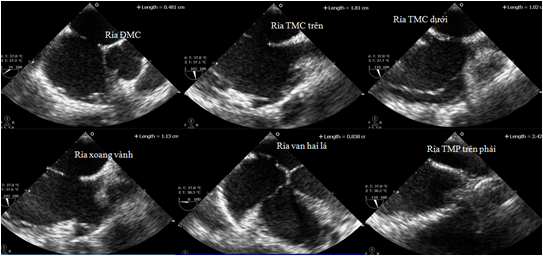

Siêu âm tim qua thành ngực (Nguồn: Internet)

Siêu âm tim qua thành ngực

Siêu âm Doppler màu qua thành ngực (Nguồn: Internet)

Siêu âm qua thực quản trong can thiệp tim bẩm sinh (Nguồn: Internet)